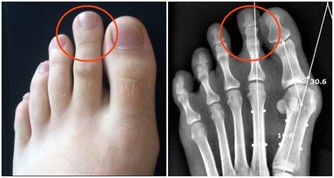

- 膝蓋、頸椎等關節部位特別容易受冷風侵襲,引起頸椎病、肩周炎、風濕、類風濕等。